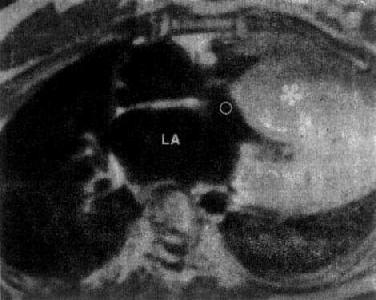

MRI是无创伤性检查方法,对下述疾病有诊断价值:①大血管病:主动脉夹层动脉瘤,能显示真假腔和内膜片;主动脉瘤,可见主动脉腔扩大,壁薄及瘤内血栓;主动脉的异常,如缩窄和扩张以及腔静脉的狭窄和梗阻。②先天性心脏病:房室间隔缺损、主动脉缩窄、动脉导管未闭和复杂性先天性心脏病。③心肌病变;心肌梗死、室壁瘤(图3-2-27)、瘤内血栓形成、特发性心肌病(图3-2-28)。④心脏肿瘤:良性粘液瘤、恶性纤维组织细胞瘤、血管肉瘤和肌肉瘤等。⑤心包病变:心包积液,心包肥厚和心包肿瘤等。

图3-2-28 特发性心肌病